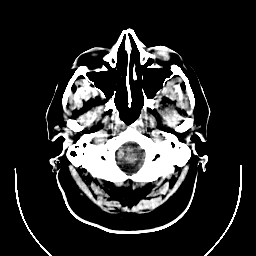

CT Study #1 -- Slice #2